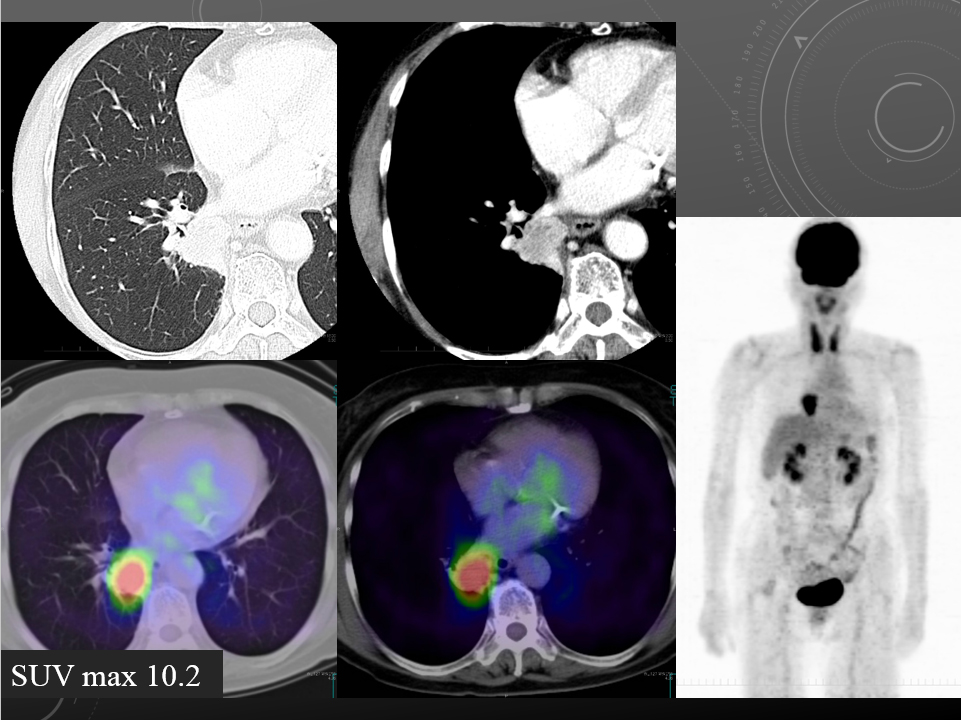

68F CEA 高値精査。消化器内科依頼。既往に脳梗塞、心筋梗塞、胃ポリープあり。

右肺下葉腺癌。

右肺下葉の縦隔側には最大径31mm大の不整形な腫瘤性病変を認めます。表面には部分的にspicula所見が見られ、胸膜に広汎に隣接するように存在しています。内部は辺縁を中心に淡い造影効果を呈しています。原発性肺癌病巣が疑われます。肺門部にはリンパ節腫大像が見られますが、縦隔領域に明らかに有意なリンパ節腫大は指摘出来ません。

左肺下葉に末梢側には淡い濃度上昇所見が見られ、GGO病変が疑われます。この他、肺野に明らかな腫瘤性病変は指摘できません。

肝内に占拠性病変は認められません。

明らかな副腎腫瘤は指摘できません。

両腎には嚢胞と考える低吸収像を認めます。

胸腹水貯留は見られません。

腹壁瘢痕ヘルニア所見を認めますが、明らかな腸管の逸脱は見られません。

・Lung cancer s/o

SUVmaxは10.2

右肺下葉内側の腫瘤に一致して異常集積を認める。